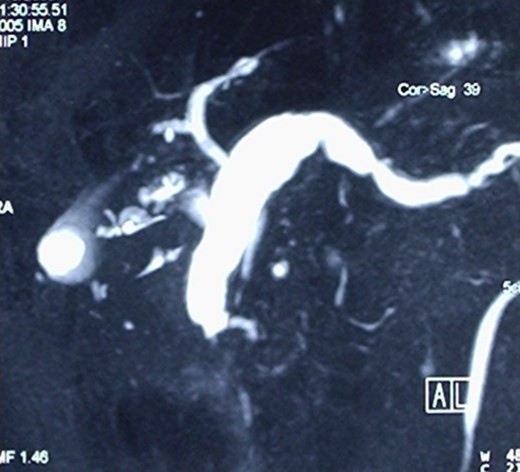

A Cholangio-magnetic resonance imaging (MRI) (Fig. 3) revealed that the sero-cystic lesion found at CT, was being mimicked by the enormously dilated pancreatic duct that had reached a diameter of 2 cm at the level of the pancreatic body. The dilation decreased to 1 cm in the pancreatic tail and the lumen of the Wirsung duct seemed to have an irregular profile. On the opposite side, the Wirsung caliber suddenly decreased in proximity to its duodenal end. This finding was not univocal and could suggest an intraductal mucous secreting tumor, chronic pancreatitis or an ampullary alteration. The pancreatic parenchyma of the body and of the tail was remarkably hypotrophic, and only some residual pancreatic tissue was observed at the uncinate process. The choledochus maintained a regular size almost down to its duodenal end, but in proximity of the Vater ampulla it disappeared for about one cm, suggesting a functional spasm or, more likely, a pathologic process of the ampulla. An octreoscan did not demonstrate any somatostatin receptor.

Cholangio-MRI, showing an enormously dilated pancreatic duct, with the diameter of 2 cm at the level of the pancreatic body mimicking the sero-cystic lesion found at CT.